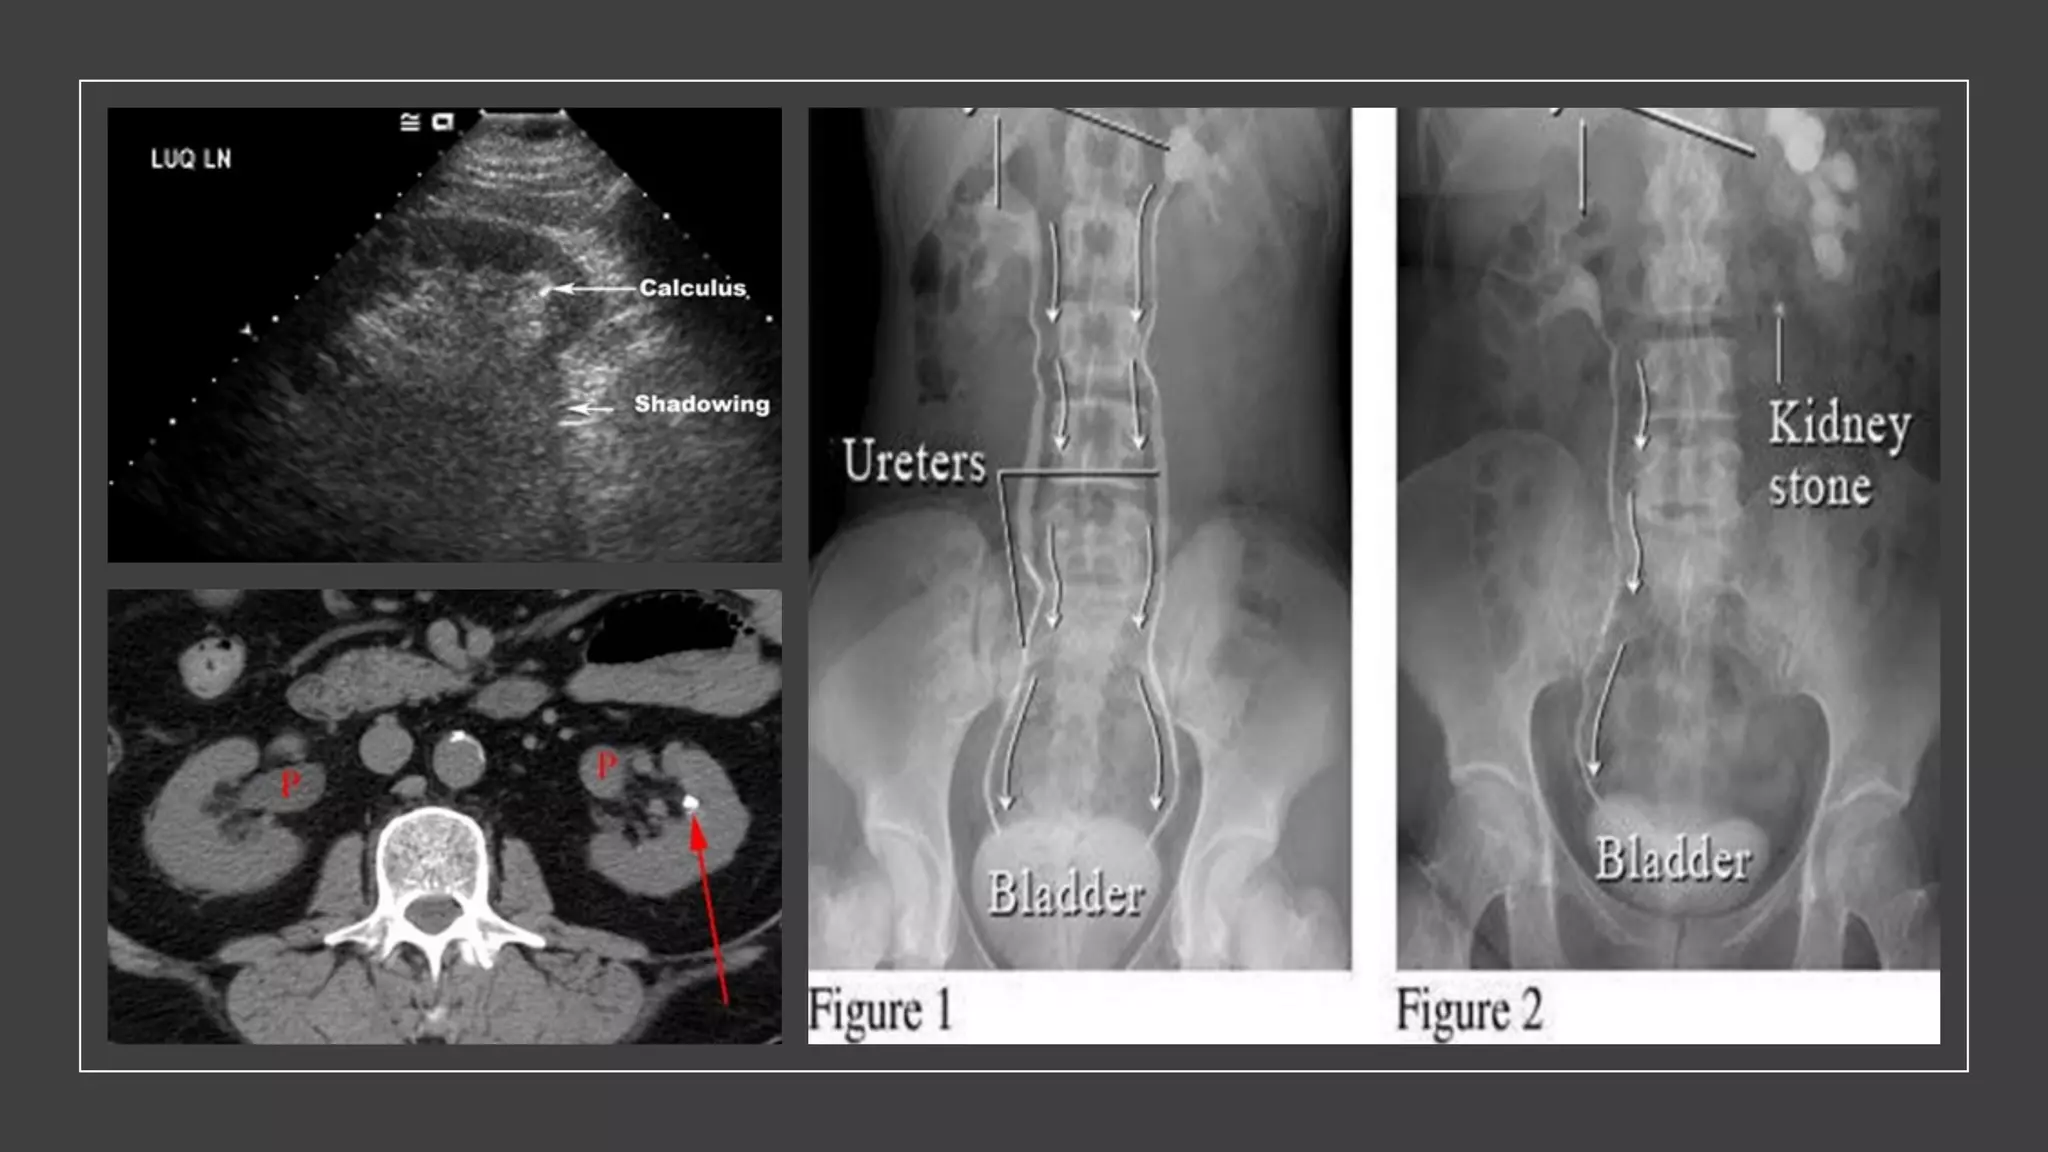

The document discusses the anatomy and physiology of the urinary system and obstructive uropathy. It describes the kidneys, ureters, bladder, and urethra, including their locations, functions, and coverings. It also discusses causes of obstruction at different levels of the urinary tract, associated clinical features, complications of obstruction like hydronephrosis, and physical exam findings.